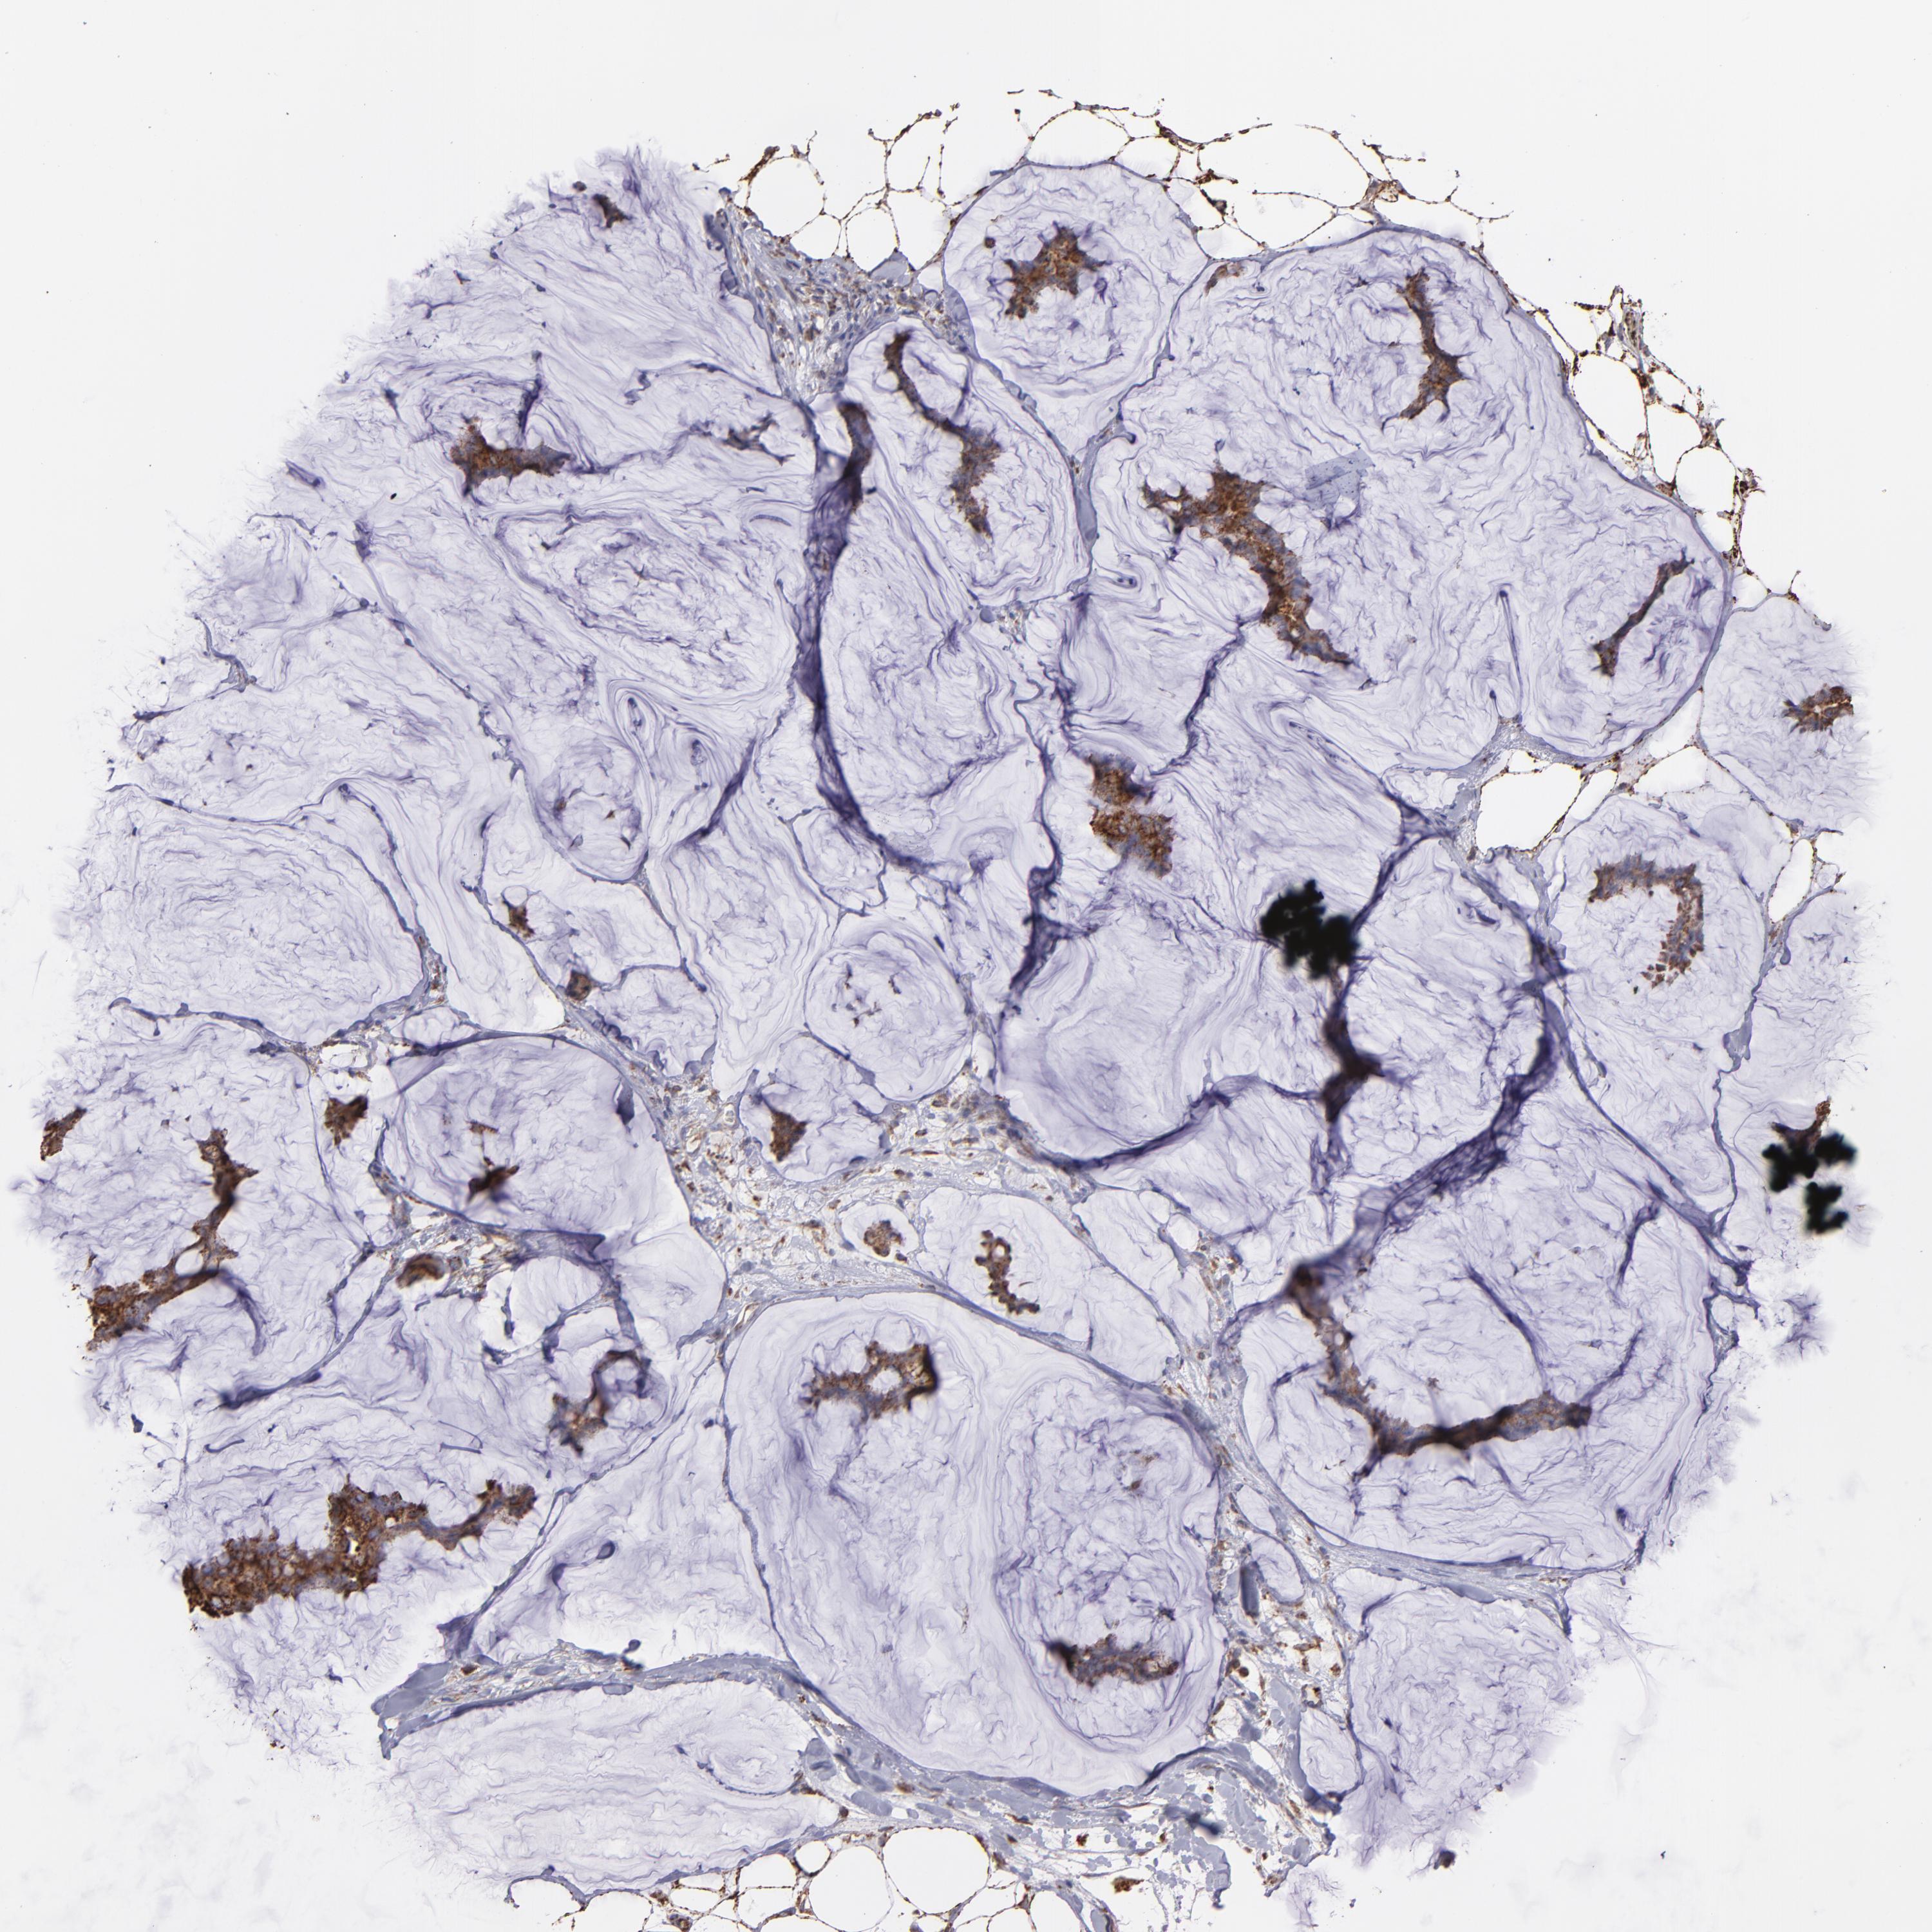

CANCER BREAST CANCER Show tissue menu

BRCA TCGA BRCA VALIDATION PROTEIN EXPRESSION